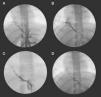

Caso 1Lactante de 3 meses con diagnóstico posnatal de canal auriculoventricular que ingresa por cuadro de dificultad respiratoria aguda por descompensación de su cardiopatía de base. En la radiografía de tórax se observa una desviación del mediastino hacia la derecha con signos de hipoplasia pulmonar derecha. Ante esta sospecha se realiza un estudio angiográfico y de parénquima pulmonar mediante tomografía computarizada (TC). El estudio de TC (LightSpeed Ultra, General Electrics, Milwaukee, Estados Unidos), realizado con baja dosis de radiación, muestra una asimetría de tamaño entre ambas arterias pulmonares, la derecha con un calibre ligeramente menor y con disminución del tamaño del pulmón derecho. A nivel retrocardíaco, entre ambas pleuras viscerales posteriores, se aprecia un lóbulo accesorio con una aferencia vascular sistémica desde el tronco celíaco de 3mm de grosor (fig. 1A y 1B) y con drenaje a la vena pulmonar inferior derecha, hallazgos compatibles con secuestro pulmonar y leve hipoplasia pulmonar.

Estudio de tórax mediante TC. A: Reconstrucción axial en filtro de pulmón. Se aprecia el lóbulo accesorio a nivel retrocardíaco entre ambas pleuras viscerales (flechas). B: Reconstrucción MIP (proyección de máxima intensidad) en proyección oblicua izquierda para valoración de la vascularización. Se aprecia una estructura vascular anómala que se origina en el tronco celíaco y se extiende cranealmente hacia la base pulmonar derecha/línea media (flecha).